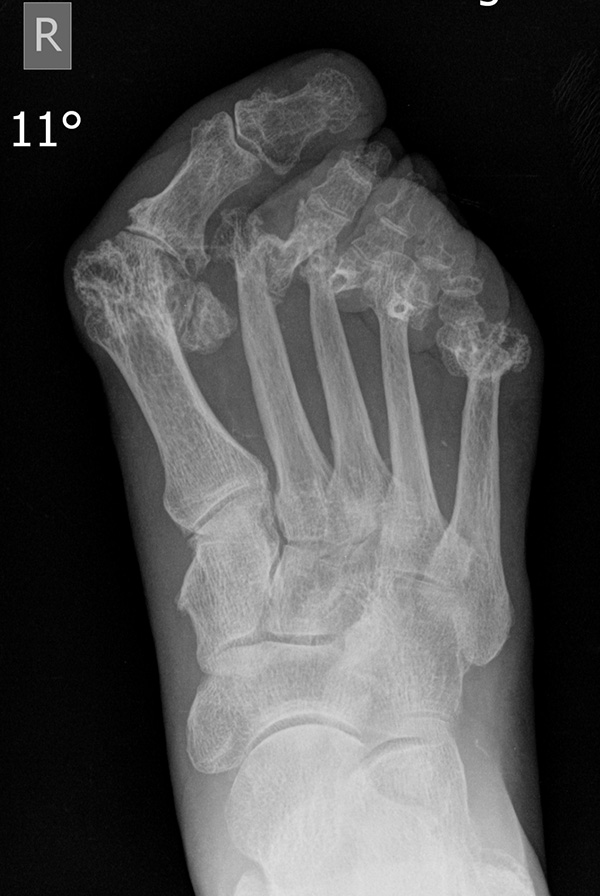

Thomas et al. 37 führten eine prospektive Kohortenstudie an 23 Patienten (37 Füßen) durch. Durchgeführt wurde die Resektion aller Metatarsaleköpfchen über drei dorsale Inzisionen. Nach 64,9 Monaten lag der AOFAS Score bei 64,5 Punkten, der durchschnittliche Hallux valgus Winkel lag bei 22,3°. Es kam zu keinen Revisionseingriffen.